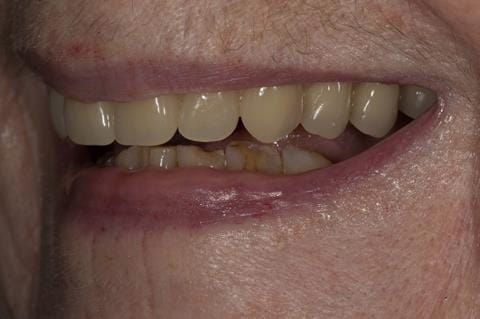

- Cobalt chromium reinforced gasket denture - using a Molloplast B "O" ring to retain and stabilise the denture. This was my professional preference as this was the least invasive and simplest solution to this dental problem. Should the UR7 require removal in the future - an artificial tooth could be added - resulting in a complete denture. The patient would have adapted to the denture fully by this stage and have good neuromuscular control of the prosthesis.

Following consultation and second discussion appointment the patient chose to have option 2 namely, a window denture - maxillary cobalt chromium based partial denture. The clinical situation and treatment process is shown in detail below with photographs. The patient was successfully rehabilitated with this and her quality of life considerably improved. The clinical work was provided by Finlay and the technical work by Rowan.